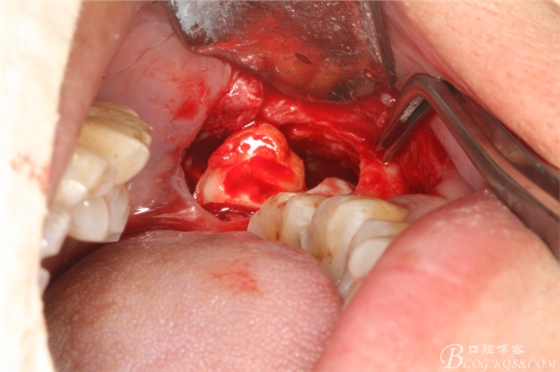

圖5.首先取出牙根

圖7.然后取出牙冠